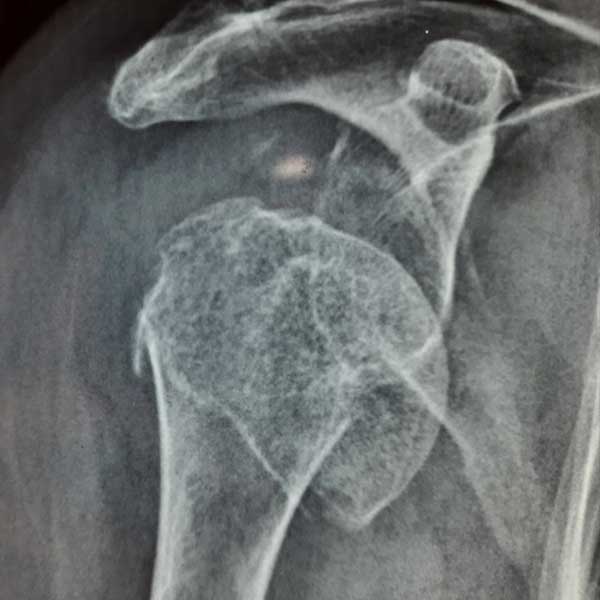

Case:2 Fracture of Neck Humerus with Fracture of Greater Tuberosity

Pre-Op AP